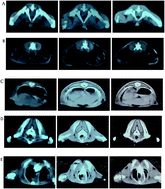

The effects of casein non-phosphopeptide (CNPP) on the muscle development of healthy rats and selected blood hormones levels were investigated. CT technology and the ELISA kit were employed to detect the cross-sectional area of each muscle group and blood hormone levels, respectively. The cross-sectional area of the trunk and lower limb muscles of resistance exercise group (REG) rats that were administered a high daily dose of CNPP for 50 days increased more significantly than that of the blank group rats, no exercise group (NEG) rats administered with the same daily dose of CNPP, and REG rats administered with the same daily dose of lactalbumin (P < 0.05).The more enhanced development of trunk and lower limb muscles in CNPP-administered REG rats was associated with a higher blood level of insulin, while no clear trends in blood levels of growth hormone and testosterone were observed. The present results have demonstrated that a combination of physical exercise and diet supplementation with CNPP can synergistically improve muscle mass.